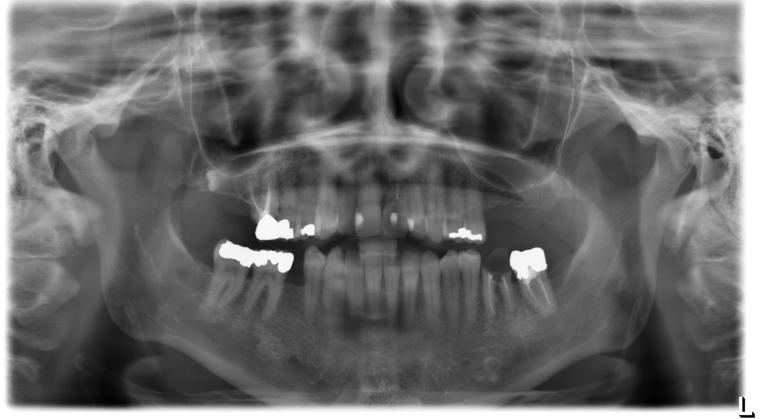

Ein Tätigkeitsschwerpunkt unserer Praxis in Salzburg ist die Implantologie. Wenn ein Zahn fehlt oder entfernt werden muss, sollte immer die Möglichkeit der Implantation im Vordergrund stehen. Ein Implantat verhält sich von den Eigenschaften genau so wie ein natürlicher Zahn. Egal ob nur ein einzelner Zahn vom Zahnarzt ersetzt werden muss oder ein ganzer Kiefer mit festsitzendem Zahnersatz versorgt werden soll, wir finden für Sie eine Möglichkeit, auch wenn die Voraussetzungen ausweglos erscheinen. Wenn möglich versorgen wir unsere Patienten mit Keramikimplantaten. Diese sind immun-neutral und können sehr oft direkt bei der Zahnextraktion eingesetzt werden. Für unsere Patienten ist daher meist nur ein operativer Eingriff notwendig!

- 3D-Röntgentechnik, 3D-Implantatplanung und virtuelle Implantation